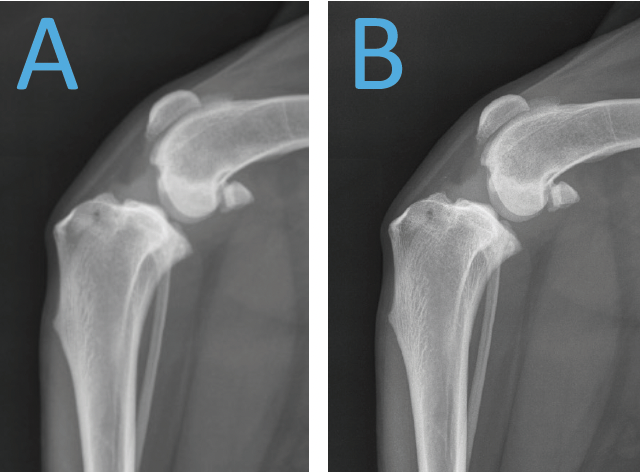

Laquelle des deux radiographies a été prise avec un filament de taille plus petite?

A

la B)

en effet, un filament plus petit offrira une radiographie avec plus de détails